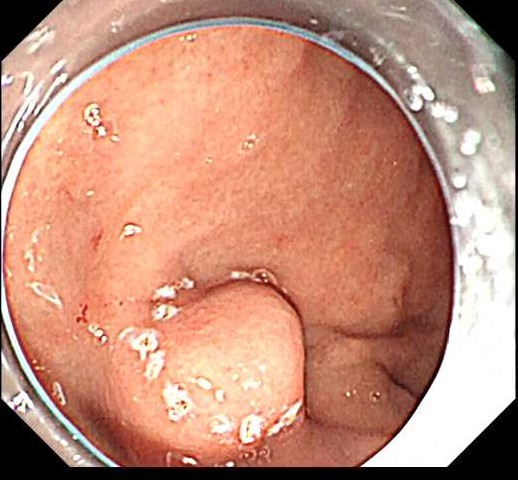

近日,毕节市中医医院脾胃病科接诊一名54岁的女性患者,主诉半年来无明显诱因出现腹胀,与进食无明显相关,不规律间断发作,就诊于脾胃病科门诊。门诊医生接诊后,为其行胃镜检查,结果提示胃底黏膜下肿物-间质瘤?为进一步治疗收住院。

入院后行超声胃镜检查,结果提示病灶来源于固有肌层,部分位于腔外,大小约2.0cm,考虑间质瘤(GIST)。行增强CT扫描,间叶组织来源可能,增强后呈渐进性、均匀性强化,未见淋巴结及远处转移。综合上述检查结果,考虑患者胃内肿瘤为胃间质瘤(GIST)。

在王旭东主任带领下,犹小乙主治医师负责手术操作,在张梓婷护士、麻醉老师胡雨微等紧密配合下,采用内镜下胃全层切除术(EFTR)为患者切除病灶。内镜切除过程中遵循无瘤原则,切除过程中保证瘤体包膜完整。